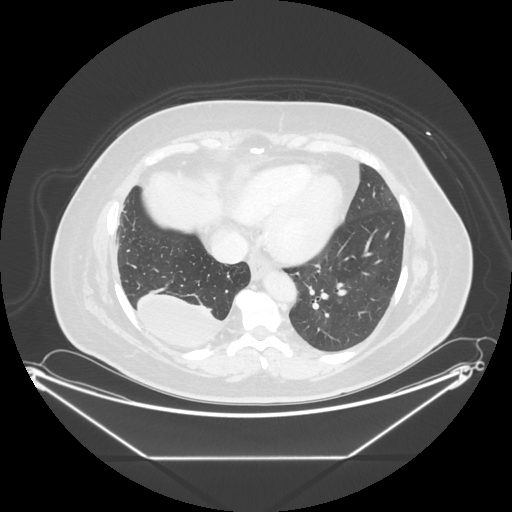

Reconstructed NATIVE CT scan (cycle consistency)

Full window (WL 1023.5, WW 4095 β†’ Low βˆ’1024, High +3071)

Lung window (WL -600, WW 1500 β†’ Low βˆ’1350, High +150)

Mediastinum window (WL 40, WW 400 β†’ Low βˆ’160, High +240)